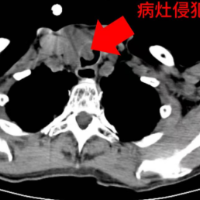

病灶图。

一年前刘老爹因甲状腺乳头状癌在外院手术,半年后出现呼吸困难,以为是肺部感染并在当地多次接受抗感染治疗,但症状持续加重。后在某县医院检查发现气管内新生物堵塞气道超过60%,病情危重,立即转入邵阳学院附属第一医院呼吸与危重症医学科。

经MDT多学科讨论,先行支气管镜下肿物切除以畅通气道并明确病理,最终确诊为甲状腺癌侵犯气管。患者经反复考虑后,选择至邵阳学院附属耳鼻咽喉头颈外科接受进一步手术治疗。